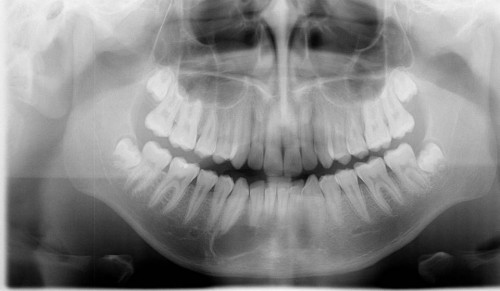

Kontrollröntgen des Unterkiefers bei einem jungen Mann

Ein 19-jähriger Patient kommt zur jährlichen Kontrolle in Ihre Praxis. Im Rahmen der Untersuchung wird eine OPAN-Aufnahme angefertigt.

Wie würden Sie den Röntgenbefund im Unterkiefer beschreiben?

- APolyzystische Aufhellung Regio 41- 43

- BScharf begrenzte, ovale Radiotransluzenz Regio 41 – 43

- CAmeloblastom Regio 41 – 43

- DFollikuläre Zyste des Zahnes 43

- EAusgedehnte Transluzenz Regio 41 – 43 mit Retention des Zahnes 43

Bildgebung - OPAN präoperativ